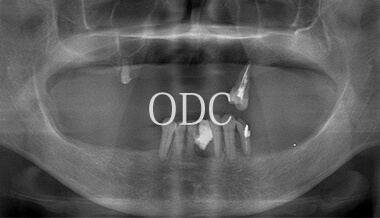

パノラマX線写真

術 前

術 後

術前・術後のパノラマX線写真です。上顎(オールオン4)は4本のインプラントにチタンフレームの上部構造が固定されているのがおわかりになると思います。下顎のインプラント埋入部位、上顎のインプラントの本数、再度写真をご覧いただくと、とてもインプラントが埋入されているとわからない程の外観、下顎の残存歯(元々の自分の歯)とも区別がつかない審美性が実現されています。